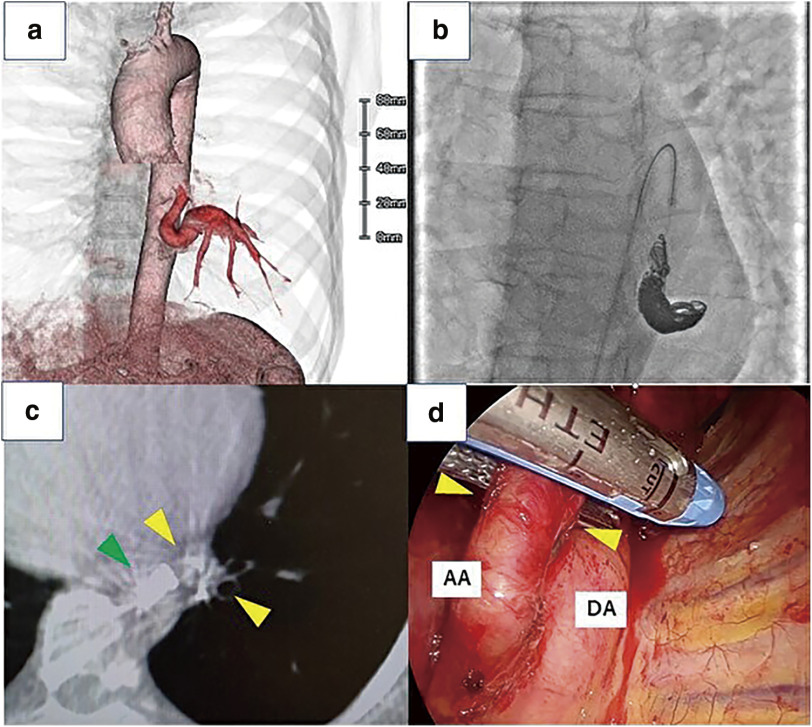

正常肺部的全身动脉供血是一种罕见的解剖异常。由于这种异常会导致肺动脉高压,因此通常需要进行手术。在此,我们报告了我们的经验和安全血管解剖的想法。病例 1 是一名 50 多岁的女性。我们在经皮线圈栓塞术后进行了左肺下叶切除术。术中通过锥形束计算机断层扫描(CBCT)确认了带有栓子的异常动脉,以便在胸腔镜手术(TS)下安全地剥离。病例 2 是一名 40 多岁的男子。经皮血管内栓塞闭塞后,我们使用吲哚青绿荧光导航进行了左侧部分切除术。术中,CBCT 成像显示了异常动脉和栓子的确切位置。这种介入放射学和TS与CBCT成像相结合的技术被认为是治疗正常肺部异常系统动脉供血的安全可靠的方法。

Systemic arterial blood supply to a normal lung is a rare anatomical abnormality. Surgery is usually indicated because this abnormality leads to pulmonary hypertension. Herein, we report our experience and ideas for safe vessel dissection. Case 1 was a woman in her 50s. We performed a left lower lobectomy following percutaneous coil embolization. The aberrant artery with emboli was confirmed intraoperatively by cone-beam computed tomography (CBCT) to safely dissect under thoracoscopic surgery (TS). Case 2 was a man in his 40s. Following percutaneous endovascular plug occlusion, we performed a left partial resection using indocyanine green fluorescence navigation. Intraoperatively, CBCT imaging demonstrated the aberrant artery and exact position of the emboli. This combination technique of interventional radiology and TS with CBCT imaging was considered safe and more secure for the treatment of anomalous systemic arterial blood supply to a normal lung.